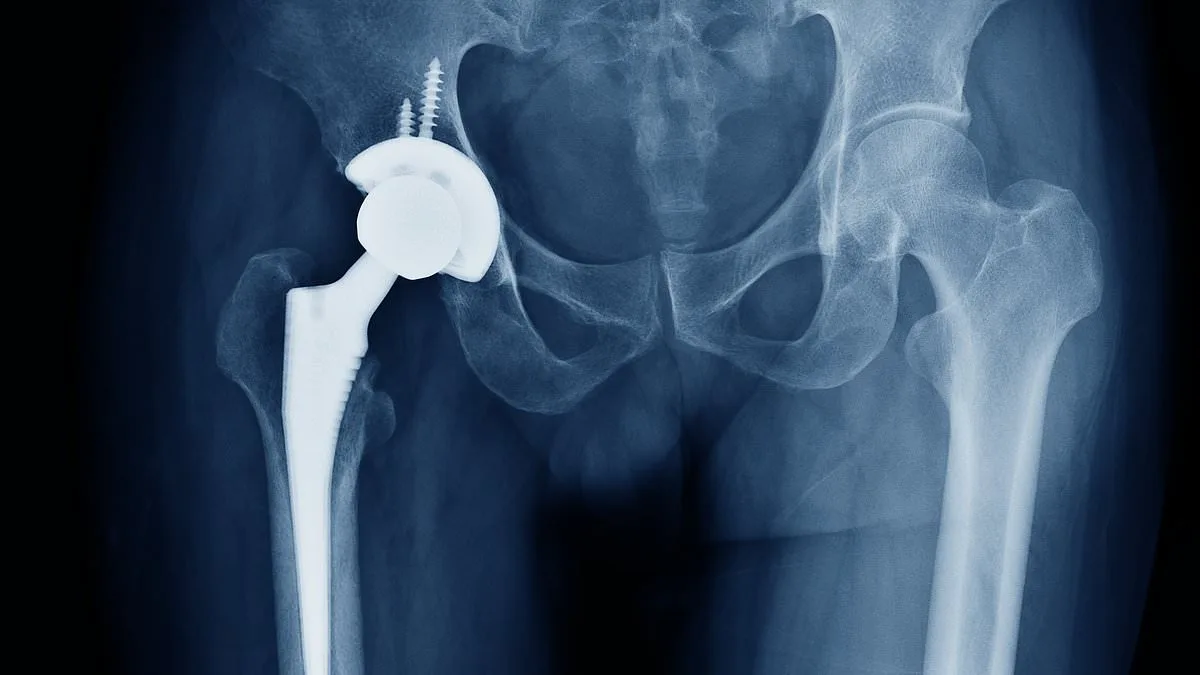

The cement acts as a high-strength grout, securing artificial joints to bone. In hip and knee replacements, it hardens rapidly to create a stable bond, ensuring implants remain firmly in place. Antibiotic-laced cements are crucial in revision cases, where infections or failed implants require temporary spacers or long-term re-fixation. Without these materials, hospitals may be forced to delay surgeries, leaving patients in chronic pain and reducing the chances of successful outcomes.